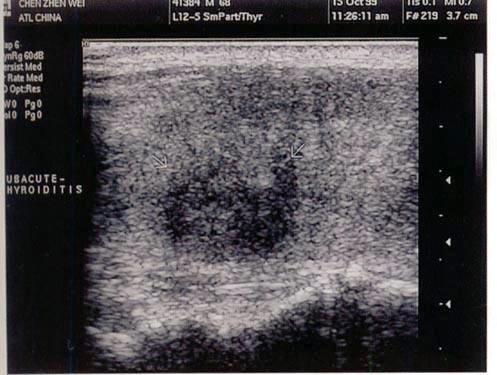

问题 患者低热,咽喉肿痛1周。发现甲状腺肿大,左侧局部压痛,结合超声声像图,最可能的诊断是?(?)

选项 A.结节性甲状腺肿 B.亚急性甲状腺炎 C.甲状腺瘤 D.甲状腺癌 E.甲状腺功能亢进

答案 B